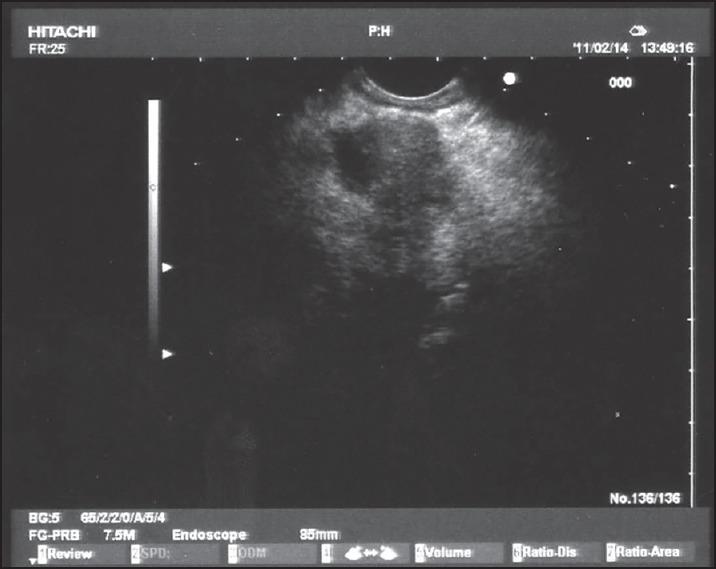

A 75-year-old man suffering from opioid-refractory due to an advanced pancreatic adenocarcinoma was treated with endoscopic ultrasound (EUS)-guided celiac plexus neurolysis (CPN) combined to EUS-guided tumor ablation. No major complications were recorded during the procedure. In the days following the procedure, mild diarrhea and fever were the only minor complications experienced by the patient. Complete tumor devascularization was assessed by means of computed tomography (CT) 48 h after the procedure. The patient remained pain-free without need of opioid, and was treated only with paracetamol for 20 weeks. Our results were optimal in terms of pain relief and immediate tumor response (assessed by means of CT and tumor marker levels). The present case demonstrates that the combined approach (EUS-guided ethanol ablation and CPN) may be a valuable option in patients with pancreatic cancer. Randomized-controlled trials are needed to confirm this result.